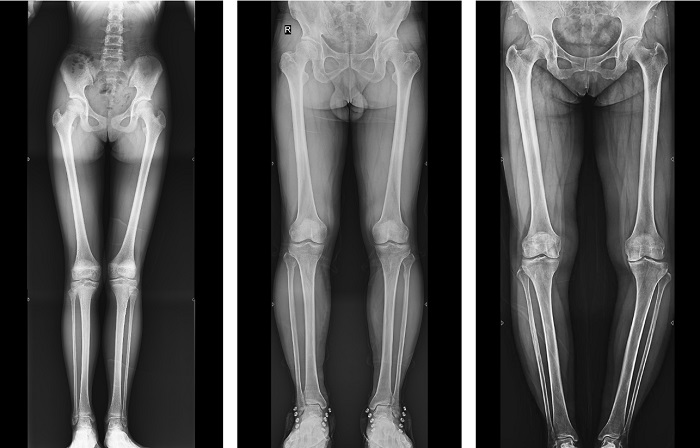

動(dòng)態(tài)DR全景拼接功能突破平板尺寸長(zhǎng)度限制,可進(jìn)行立臥位攝影,對(duì)脊柱、下肢及下肢靜脈造影進(jìn)行分段攝片,然后對(duì)分段圖像進(jìn)行拼接,在一幅X光圖像上完整顯示全脊柱或下肢整體形態(tài),獲得全脊柱或全下肢圖像,有效解決了傳統(tǒng)X光片不能一次成像問題,通過直觀顯示脊柱和下肢的整體解剖形態(tài)及側(cè)凸部位,為臨床治療提供重要參考依據(jù)。

▲全下肢DR影像

普利德多功能動(dòng)態(tài)DR進(jìn)行全脊柱全下肢圖像拼接時(shí),影像密度均勻、清晰、接緣處過渡自然,圖像質(zhì)量高,完全能滿足臨床觀察、診斷及測(cè)量要求。拍片過程也更加方便快捷,使患者得到快速診斷,及時(shí)治療,為臨床醫(yī)生和患者帶來更大的便利,大大助力醫(yī)院醫(yī)療服務(wù)能力的提升!